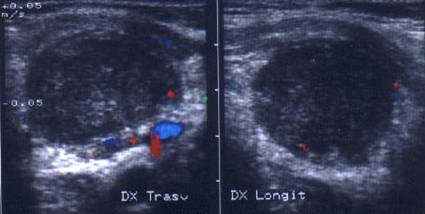

Lob drept , proiectie trasversala si longitudinala.

Femeie 19 ani. Leziune marcant hipoecogen cu intarire posterioara, de 16x20x26mm (4 cc) in lobul drept.

Examen citologic: macrofagi, fara tireocite.